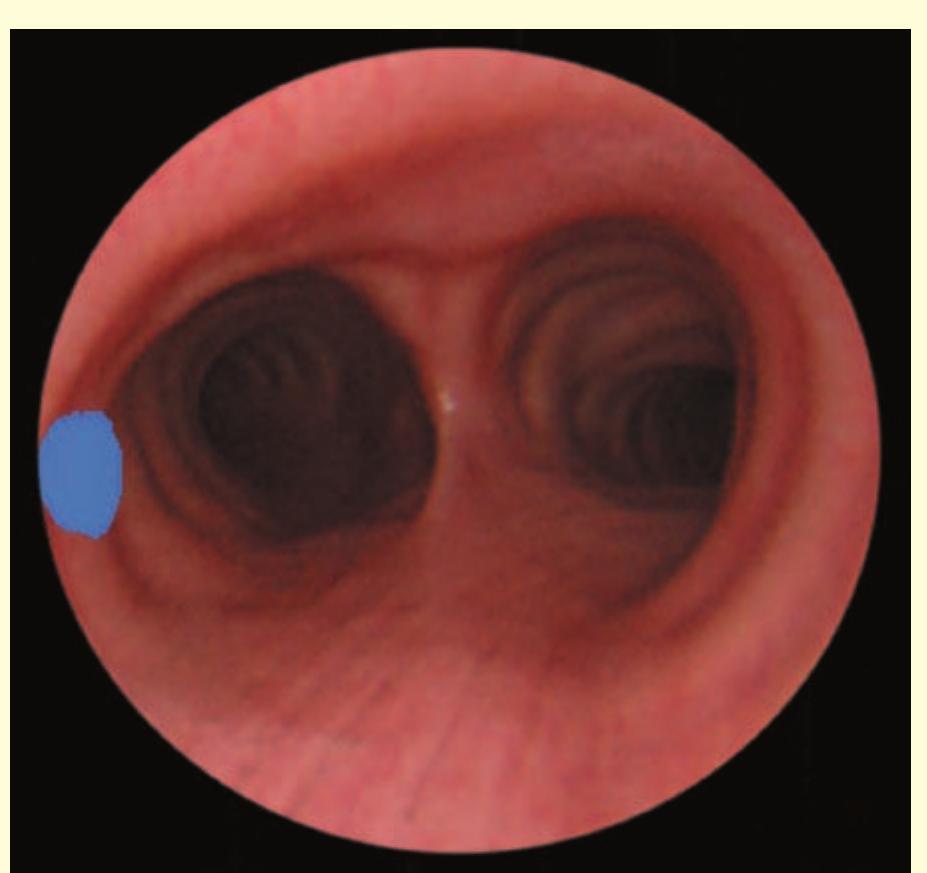

- The bronchoscope is then rotated anticlockwise by 150° to examine the subcarinal lymph nodes (station 7), extending down to the distal margin of the bronchus intermedius.